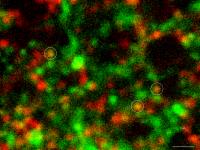

To obtain a detailed view of synaptic activity, Sulzer’s team collaborated with the laboratory of Dalibor Sames, PhD, associate professor of chemistry at Columbia, to develop a novel compound called fluorescent false neurotransmitter 200 (FFN200). When added to brain tissue or nerve cells from mice, FFN200 mimics the brain’s natural neurotransmitters and allows researchers to spy on chemical messaging in action.

Using a fluorescence microscope, the researchers were able to view the release and reuptake of dopamine—a neurotransmitter involved in motor learning, habit formation, and reward-seeking behavior—in individual synapses. When all the neurons were electrically stimulated in a sample of brain tissue, the researchers expected all the synapses to release dopamine. Instead, they found that less than 20 percent of dopaminergic synapses were active following a pulse of electricity.

"Why are there these large reservoirs of synapses that are silent?” said Dr. Sames, a co-author of the paper. “Perhaps these silent terminals hint at a mechanism of information coding in the brain that’s yet to be revealed.”